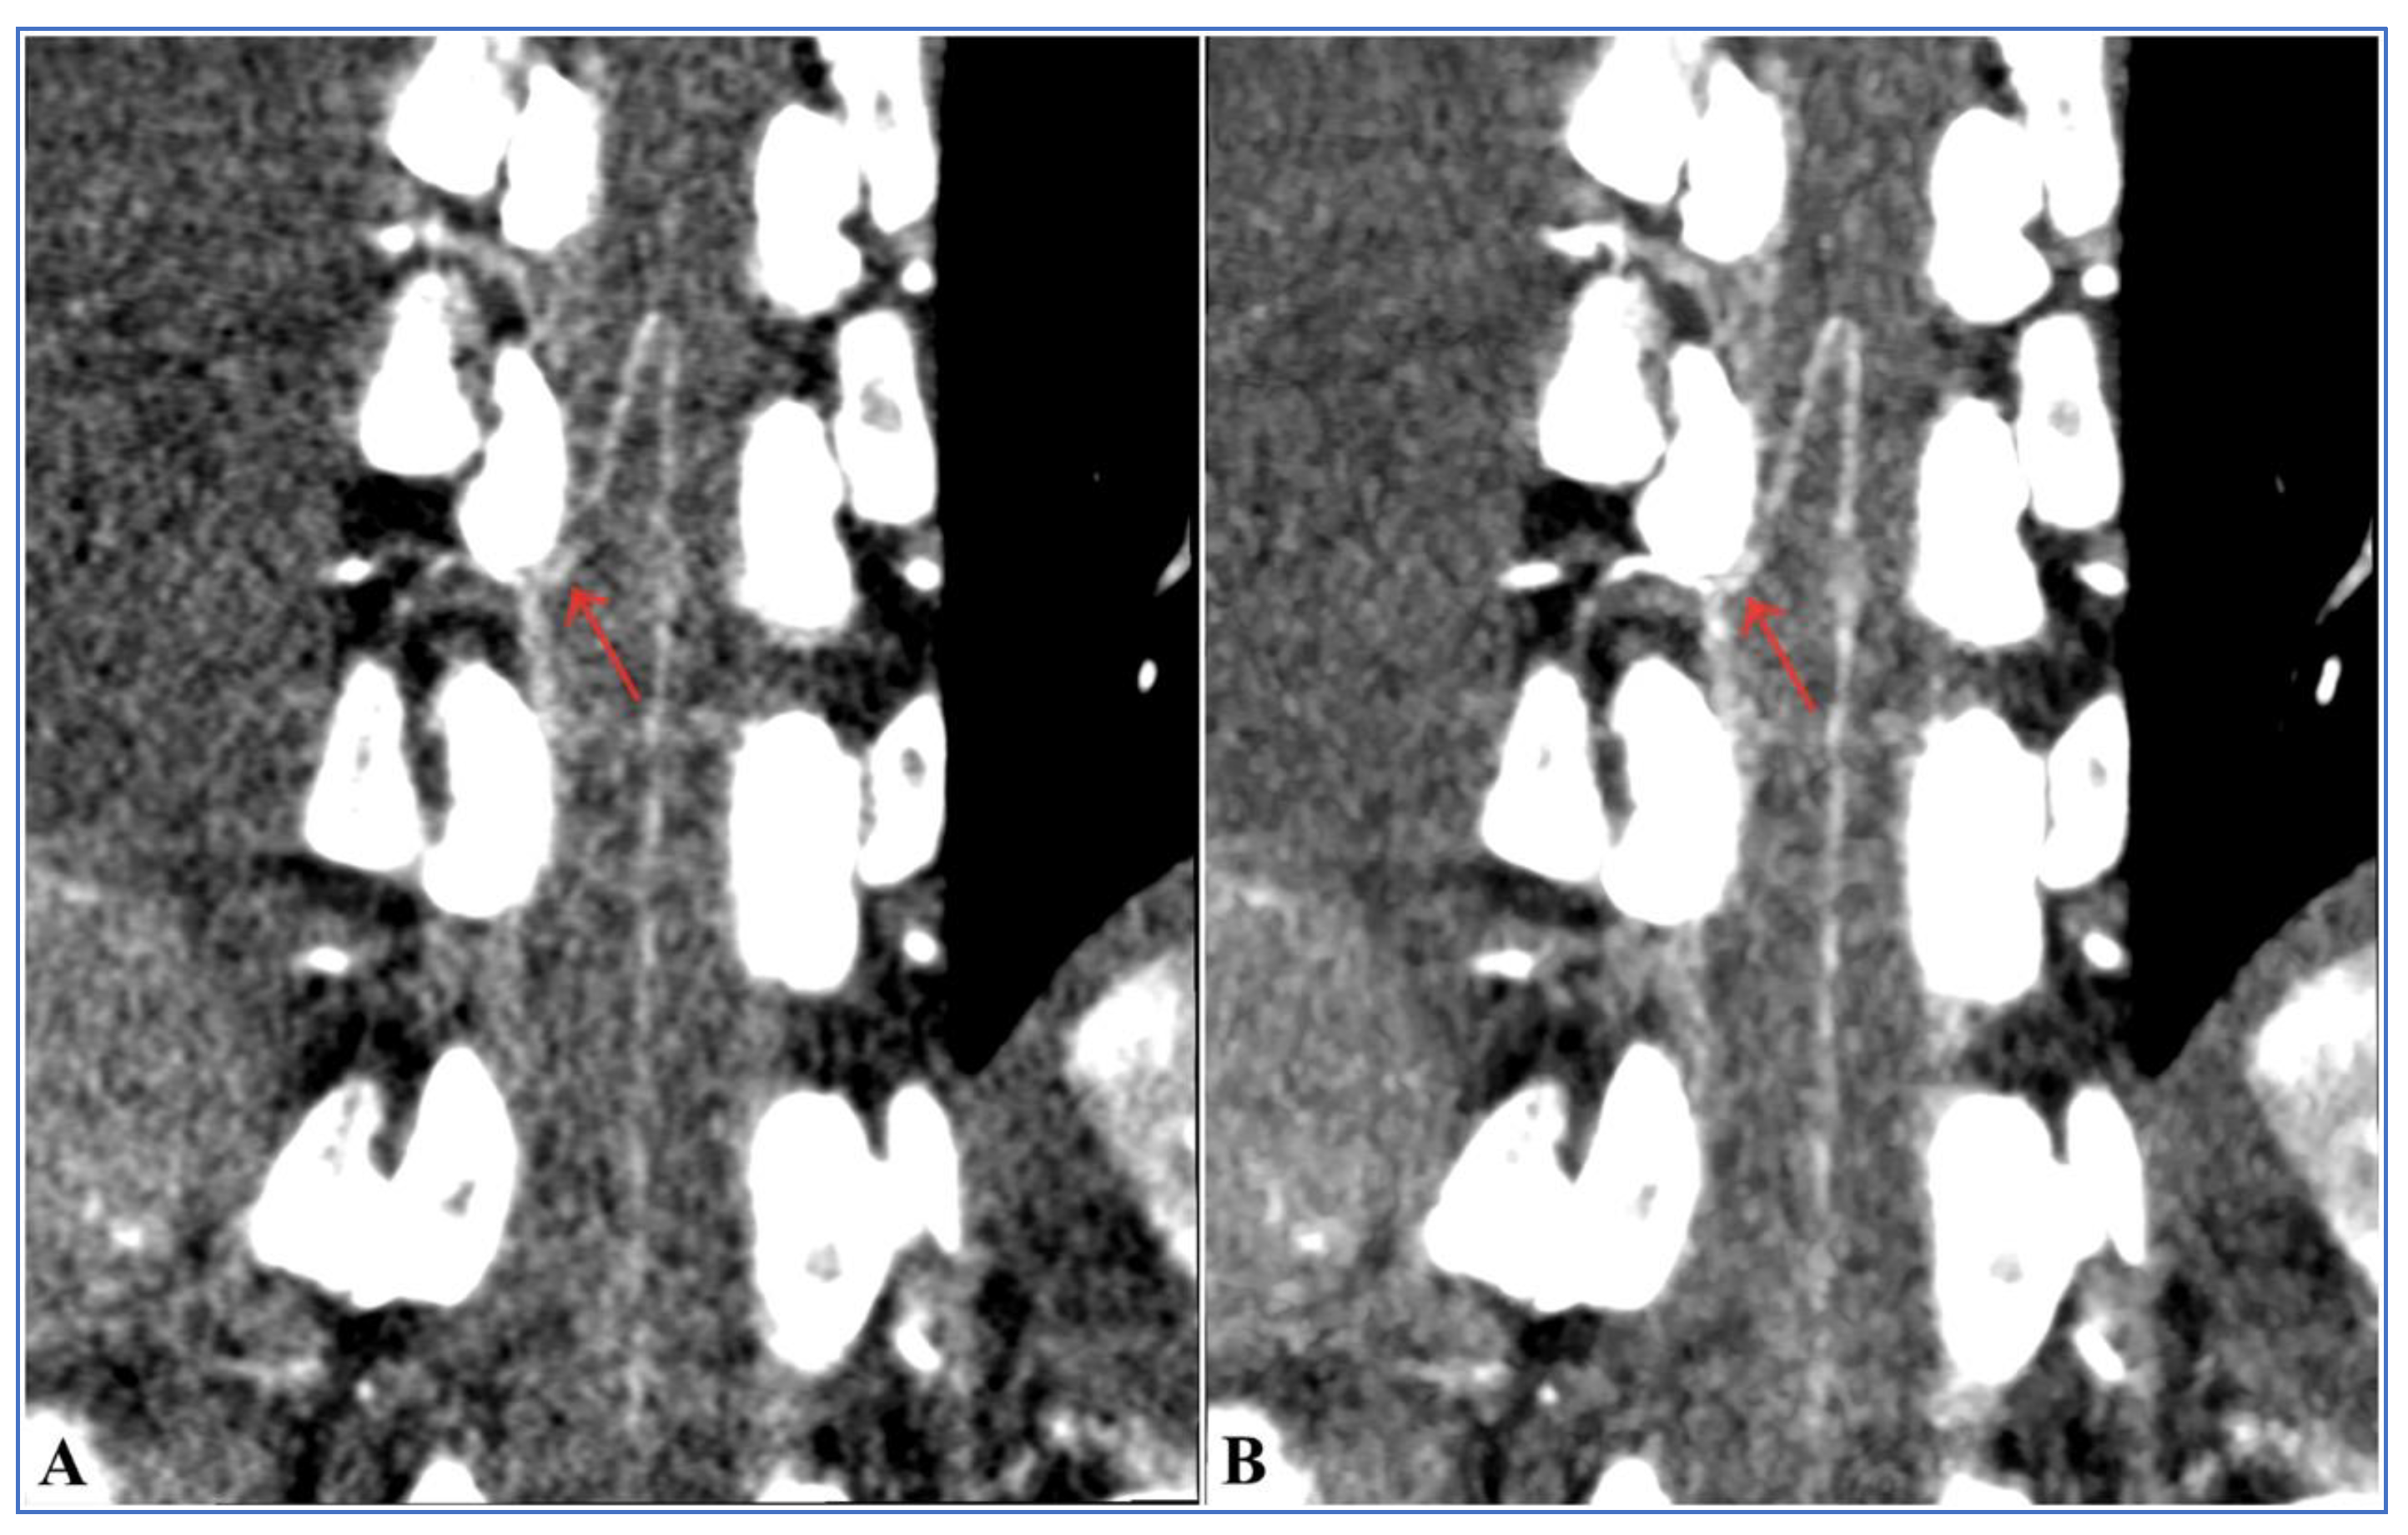

3.4. Visual Analysis of the AKA